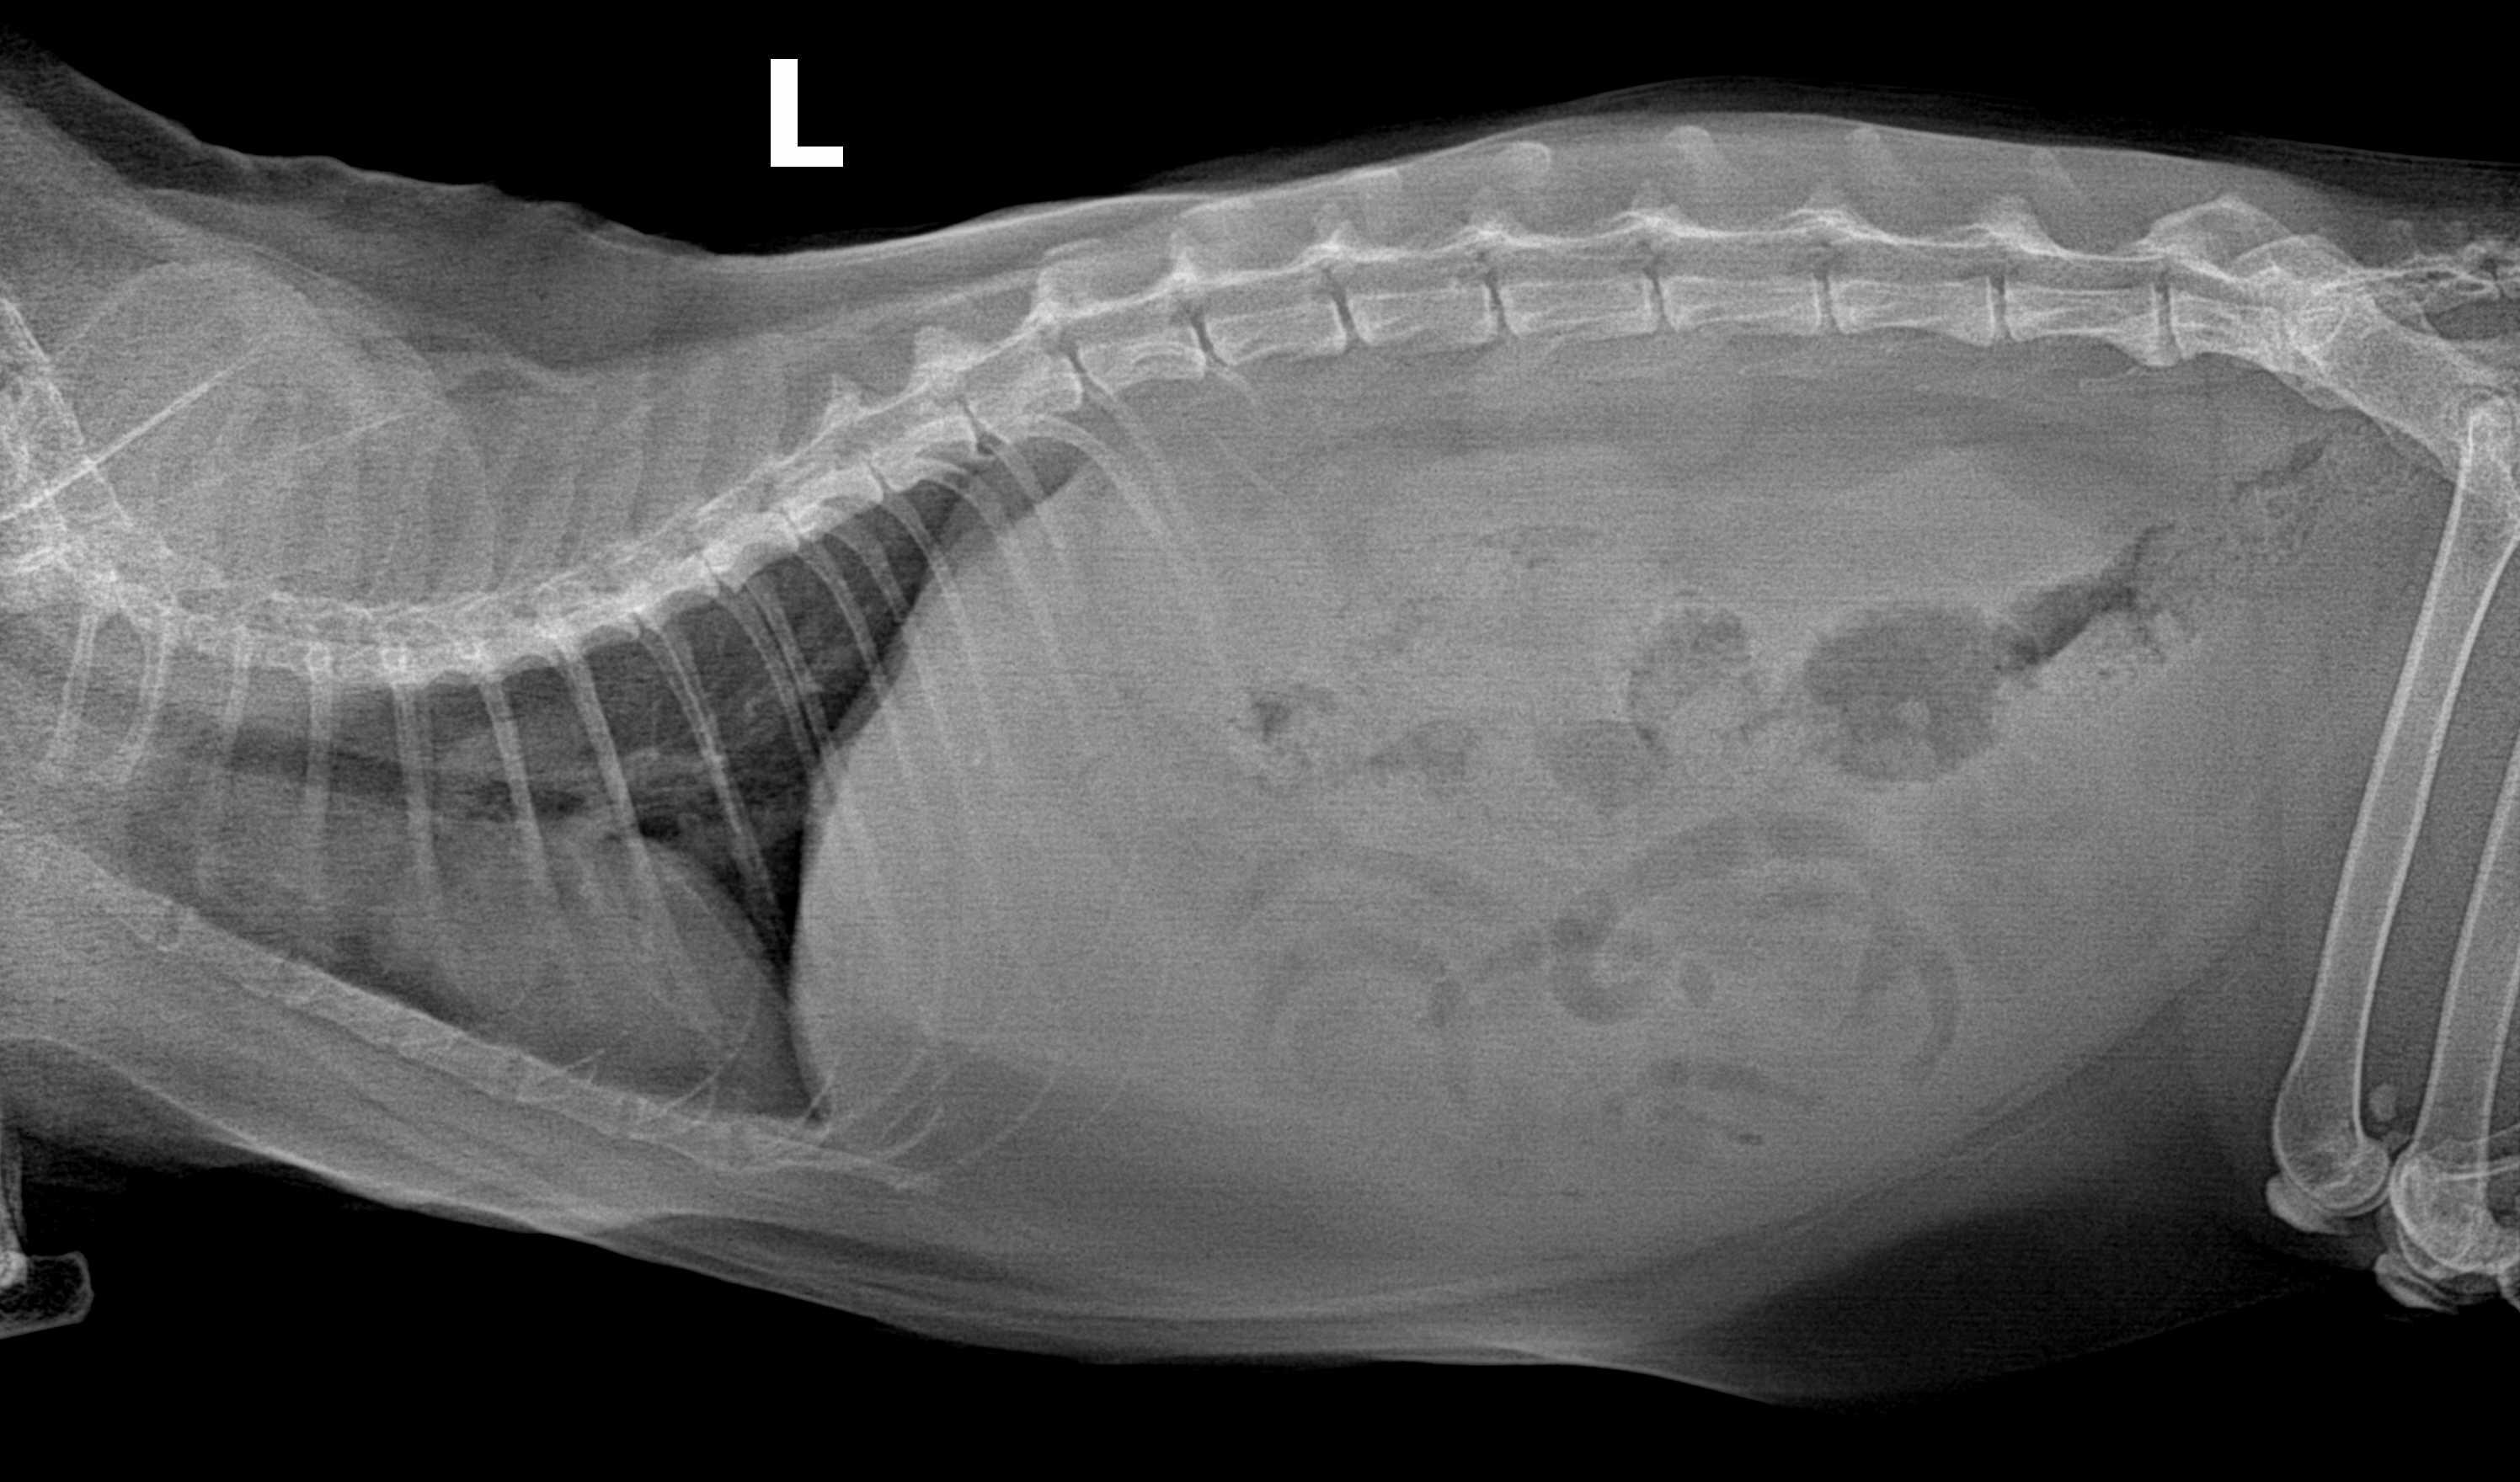

Took my cat to our local vet on Thursday for a bloated abdomen. No other symptoms. Vet found fluid in the abdomen on the xray and increased white blood cell count and said we need an ultrasound to get a real diagnosis. To get one in a timely fashion, we'll need to go to the ER. If the cat is eating, active, and showing no signs of distress, should we go ASAP or wait until Monday morning?

In my opinion going to the ER would be best, although you may not be able to have a full ultrasound until Monday morning. Some potential causes of fluid in the abdomen include an infection or abscess in the abdomen, diseases like FIP, or cancer. If there were an infection it would be best to start treatment sooner rather than later. An ER vet could take a sample of fluid to examine for signs of white blood cells or bacteria and might be able to perform a limited ultrasound. It's also possible that a specialist could be called in to perform a full ultrasound if needed over the weekend.

My recommendation for this would be the sooner you get an answer the better. As whatever is causing the fluid accumulation could potentially worsen overnight. It sounds like he is stable at the moment but that may change. I would encourage you to get him in for diagnostics sooner rather than later but if it is not possible for you to get him into the ER and want to wait, then I would wait no longer than Monday if you can help it. I am concerned that with his age, this may be something malignant or infectious. If you have any other questions / concerns feel free to contact me

If he is acting normally you can wait until Monday. If he should start to have breathing problems or stops eating go in earlier. If they did not run a blood panel they will recommend that also. The liver is enlarged on the X-ray so they may also want to do a needle aspirate to get cells to look at under the microscope. They will look at all the abdominal organs during the ultrasound and get a sample of the fluid also. Then when they get a diagnosis they can develop a treatment plan. Thanks for using Petco Pet Education Center, formerly Petcoach to help you care for NCK.